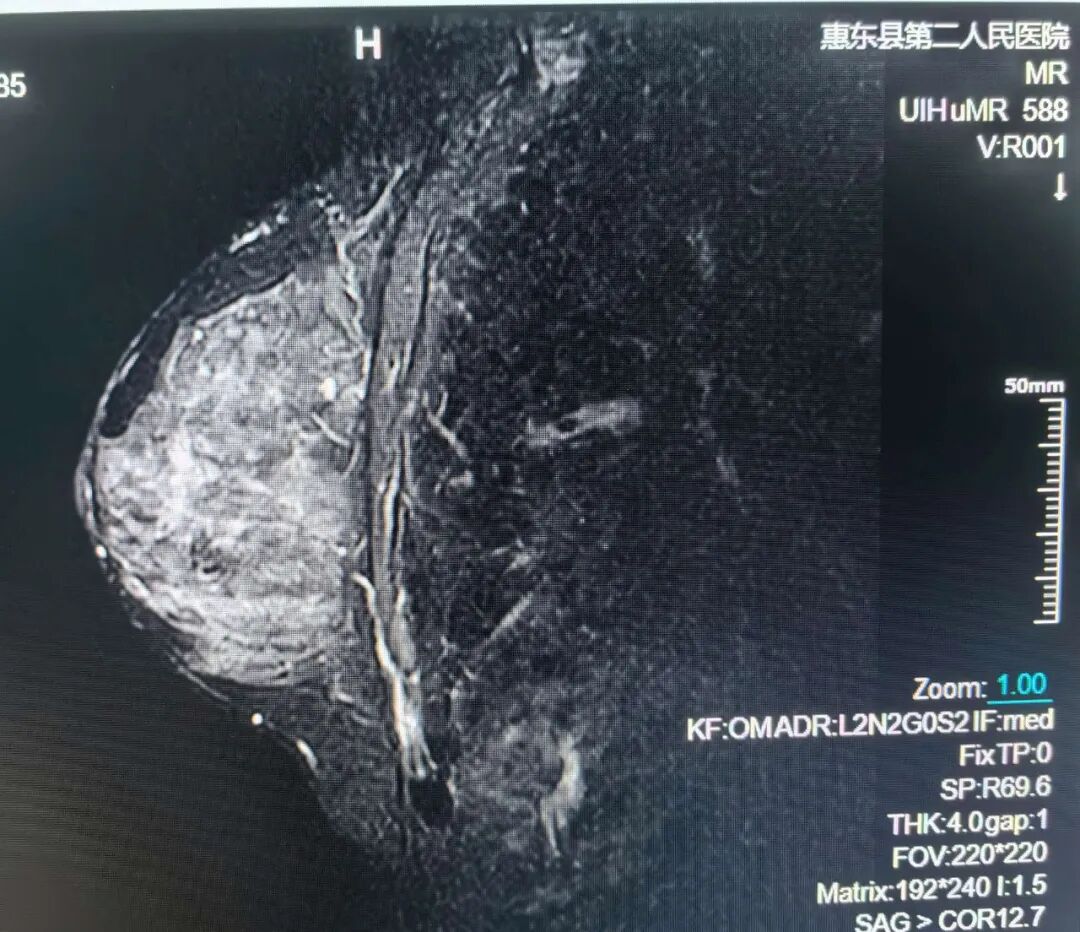

乳腺MRI检查

乳腺的良、恶性病变;高危人群乳腺癌筛查;新近诊断乳腺癌患者对侧乳腺的筛查等。